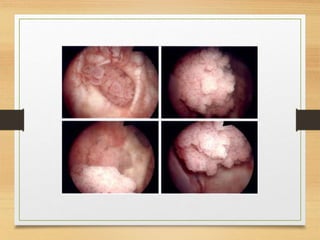

Case 1

• A 65-year-old woman is referred with total painless

haematuria. A midstream specimen of urine (MSU)

has been sent for microscopy, culture and sensitivity.

Microscopy shows a normal white cell count (WCC),

over count red blood cells (RBCs) per high-powered

field and no growth has been found on culture. She

has moderate irritative voiding lower urinary tract

symptoms (LUTS).The patient also gave a history of

anorexia, weight loss, and night sweating . No other

investigations have been performed. How would you

assess this woman?